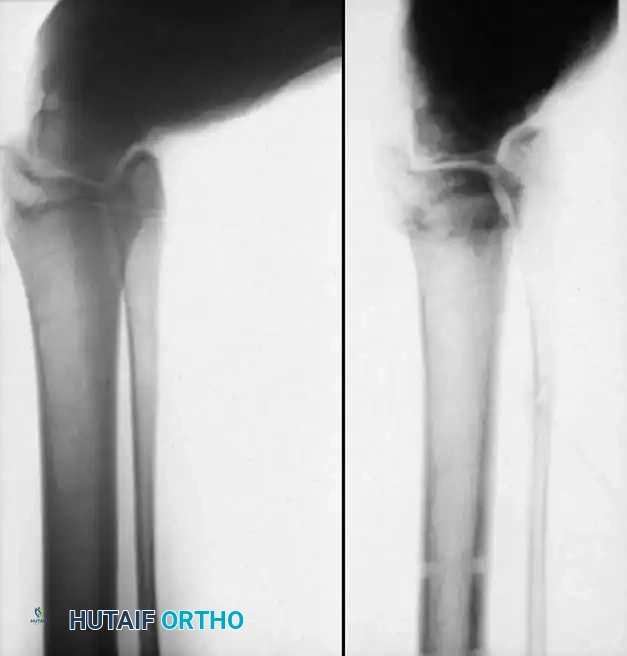

نتفهم تماماً حجم القلق والتساؤلات التي تدور في ذهن كل أب وأم عند تشخيص طفلهم بحالة الشلل الدماغي، وخاصة عندما يبدأ هذا التأثير بالظهور على طريقة مشي الطفل وشكل قدميه. تعتبر تشوهات القدم في الشلل الدماغي من أكثر التحديات الطبية شيوعاً، حيث تؤثر على نسبة تتراوح بين سبعين إلى تسعين بالمائة من الأطفال المصابين بهذه الحالة.

القدم هي الأساس الذي يرتكز عليه جسم الإنسان، وأي خلل في توازنها يؤثر بشكل مباشر على قدرة الطفل على المشي، وبذل المجهود، وممارسة حياته اليومية. في هذا الدليل الطبي الشامل والمفصل، سنأخذكم في رحلة علمية مبسطة لفهم طبيعة هذه التشوهات، أسبابها، وكيفية تطورها، وصولاً إلى أحدث بروتوكولات العلاج التحفظي والجراحي المعتمدة عالمياً لضمان أفضل جودة حياة لطفلك.

تشريح القدم وتأثير التشنج العضلي في الشلل الدماغي